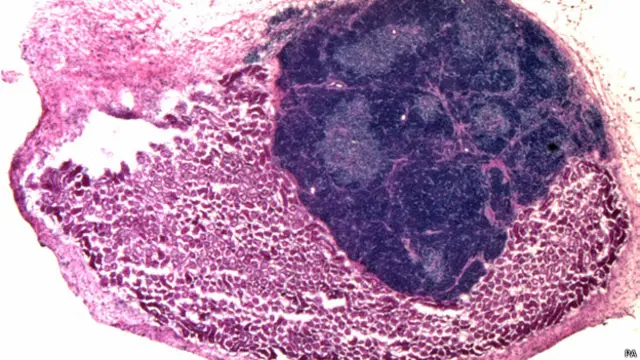

இப்படிப்பட்ட கழுத்துக்கணையத்தைத்தான் தற்போது ஸ்காட்லாந்தின் எடின்பர்க் பல்கலைக்கழக விஞ்ஞானிகள் ஒரு விலங்கின் உடலுக்குள் செயற்கையாக உருவாக்கியிருக்கிறார்கள். முதல்கட்டமாக எலியின் கருப்பையில் இருக்கும் சிசுவின் உயிர்க்கலன்களை பிரித்தெடுத்த விஞ்ஞானிகள், அவற்றை தைமஸ் எனப்படும் கழுத்துக்கணையத்தில் இருக்கும் உயிர்க்கலன்களைப்போல மாற்றி அமைத்தார்கள். இந்த உயிர்க்கலன்களுடன் கழுத்துக்கணையத்தில் இருக்கும் மற்ற துணை உயிர்க்கலன்களுடன் இணைத்து, இந்த எல்லா உயிர்க்கலன்களையும் மீண்டும் எலியின் உள்ளே கொண்டுபோய் பதிய வைத்தனர்.

இப்படி பதியப்பட்ட தனித்தனி செல்கள் ஒன்றாக சேர்ந்து புத்தம்புது கழுத்துக்கணையமாக உருவெடுத்தன. இப்படி உருவான கழுத்துக்கணையம் இயற்கையான கழுத்துக்கணையத்தைப்போல டி செல்களை உற்பத்தி செய்து இயங்கவும் துவங்கியது விஞ்ஞானிகளை வியப்பில் ஆழ்த்தியிருக்கிறது.